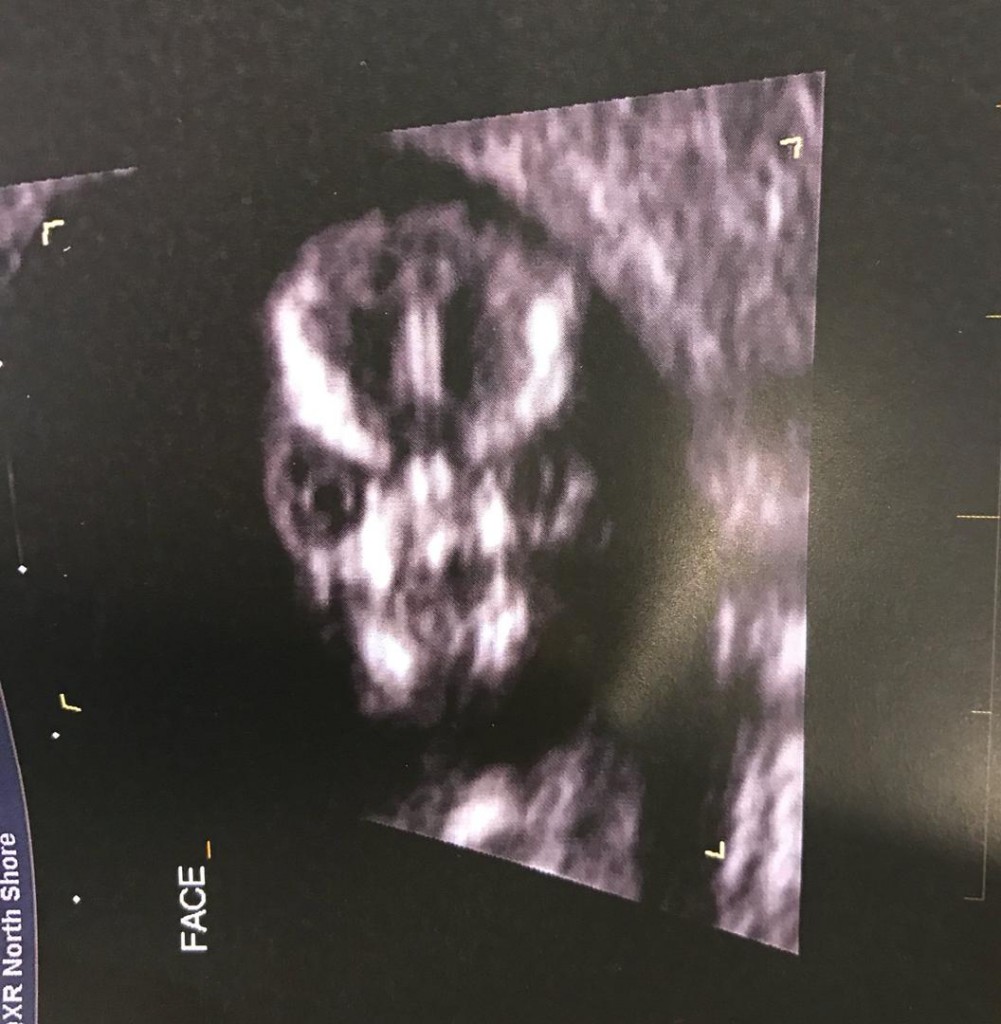

Naime, glava djeteta izgleda poput mrtvačke lubanje pa je majka fotografiju odlučila podijeliti na Twitteru.

- Tehničar na ultrazvuku odlučio je napraviti snimku lica djeteta s prednje strane i to je najstrašnija stvar koju sam u životu vidjela - napisala je ona na Twitteru.

Ona se na takve neumjesne komentare nije obazirala već je samo objasnila da tako zapravo ljudska lubanja izgleda na snimkama ultrazvuka.